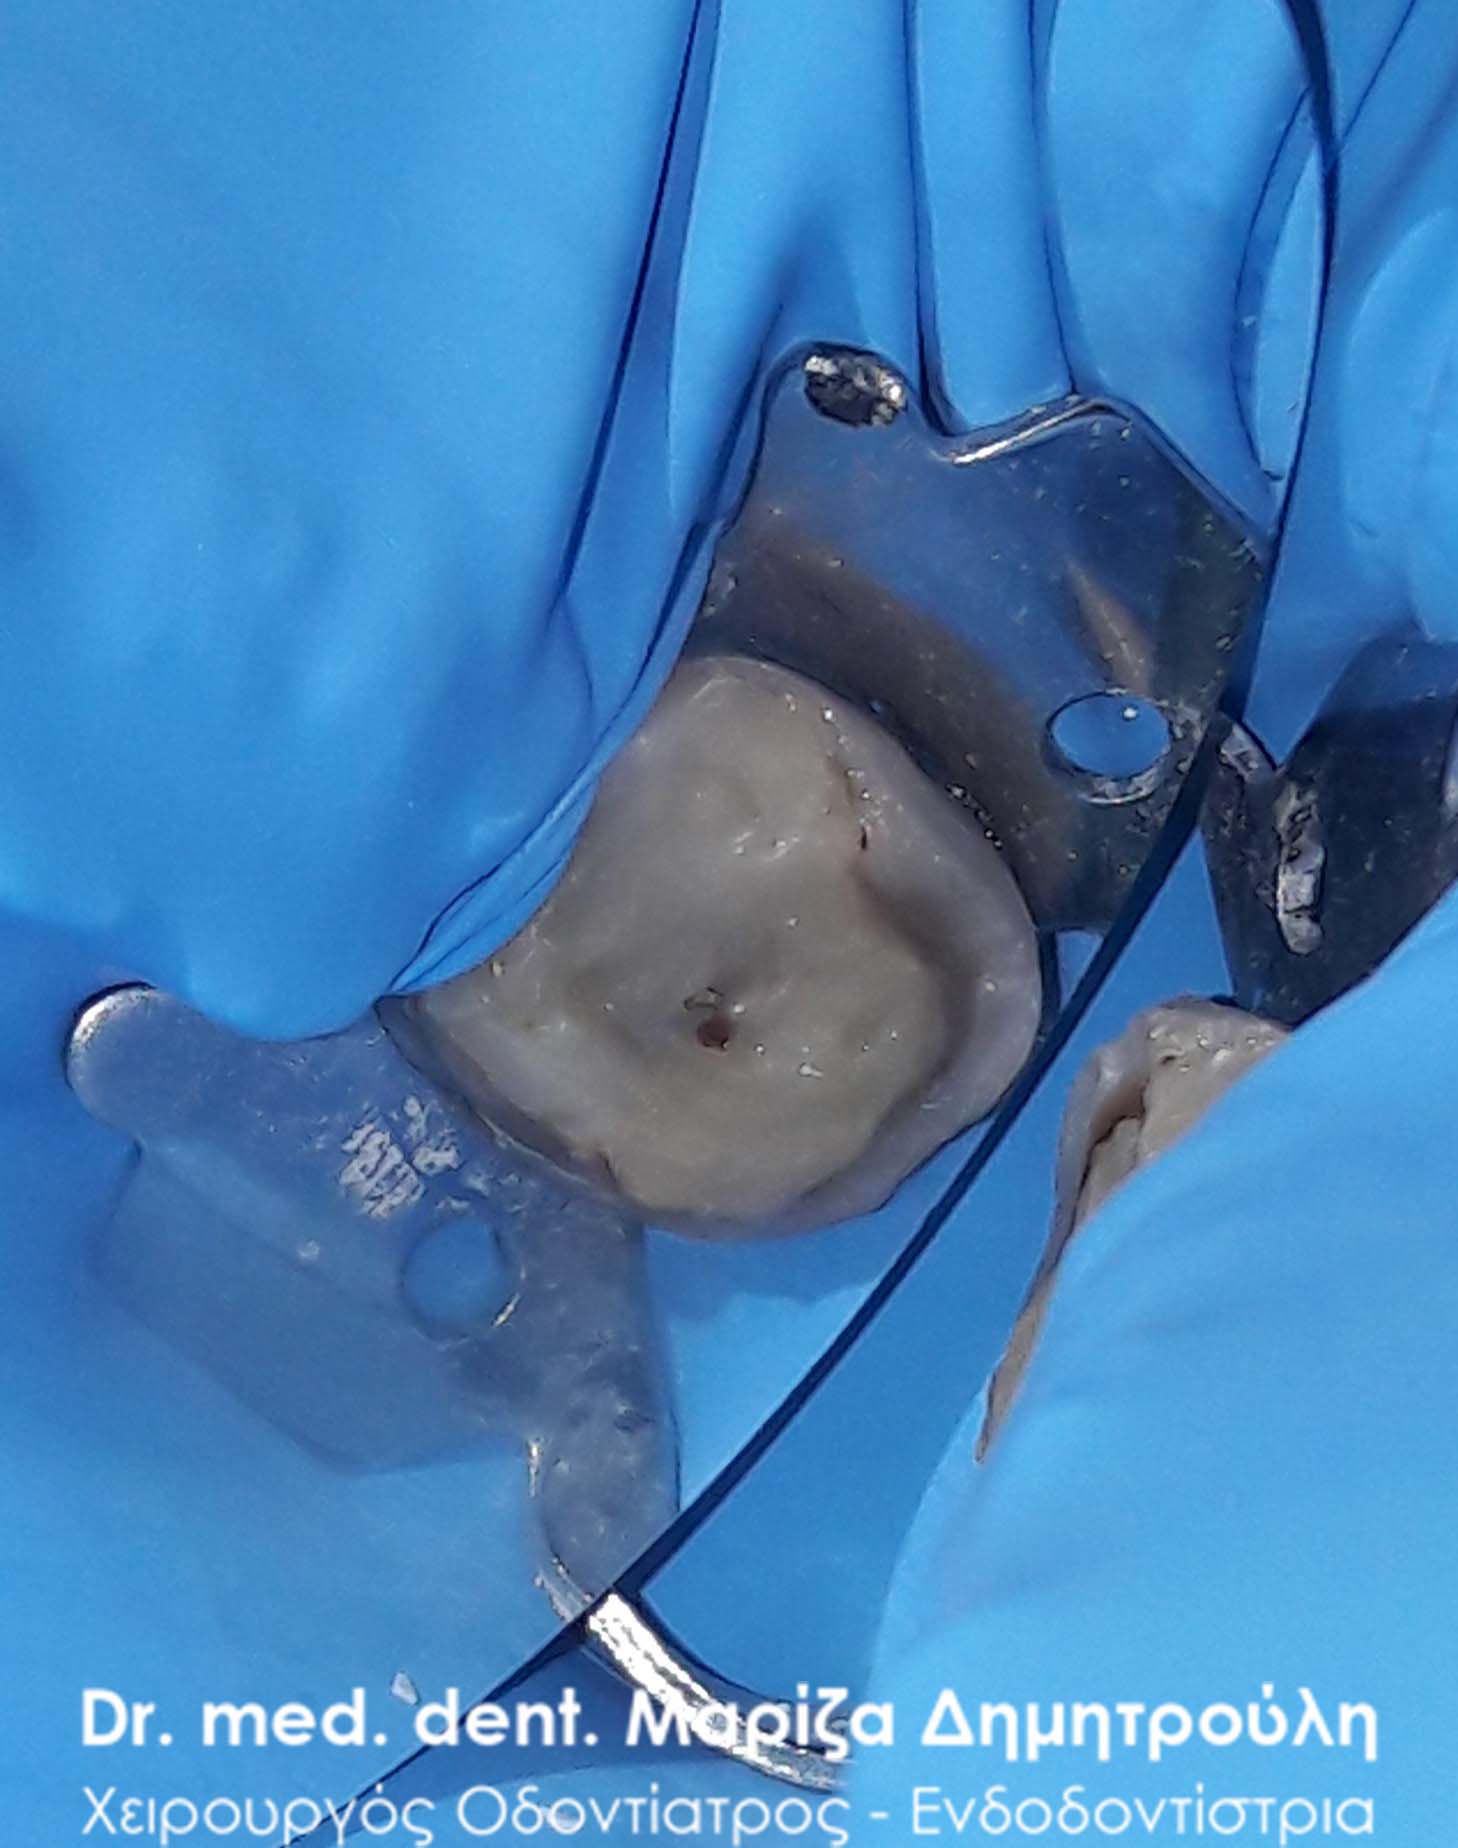

Η ασθενής είχε ένα παλιό σπασμένο σφράγισμα ρητίνης το οποίο έχριζε ανάγκη αντικατάστασης. Μετά την αφαίρεση του παλιού σφραγίσματος και την απομάκρυνση της τερηδόνας διαπιστώθηκε οτι τα μικρόβια είχαν φτάσει και είχαν προσβάλλει το νεύρο του δοντιού. Επομένως το δόντι θα έπρεπε να απονευρωθεί και στη συνέχεια να αποκατασταθεί προσθετικά. Δεδομένου οτι το οδοντικό έλλειμμα ήταν μεγάλο σε συνδυασμό με το γεγονός οτι το δόντι ήταν πλέον απονευρωμένο αποφασίστηκε η προστασία του δοντιού με ολοκεραμικό ένθετο.

Αρχική κλινική εικόνα του παλιού σπασμένου σφραγίσματος

Εικόνα του δοντιού πριν τη λήψη αποτυπώματος